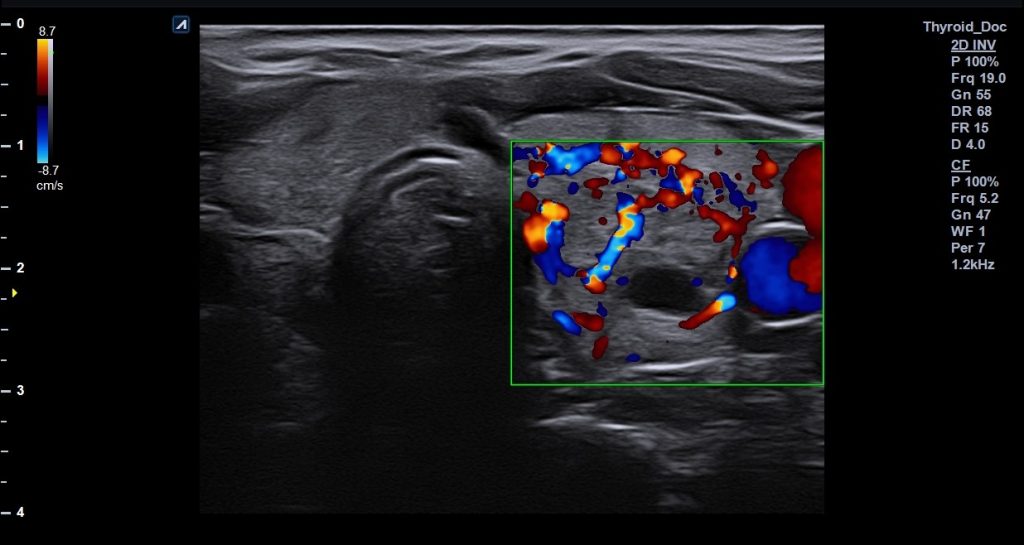

- Μύες, αγγεία και άλλοι ιστοί του τραχήλου: Η εξέταση επιτρέπει την παρακολούθηση των μαλακών μορίων και της κυκλοφορίας του αίματος στην περιοχή, καθώς και τον εντοπισμό πιθανών βλαβών ή ανωμαλιών.